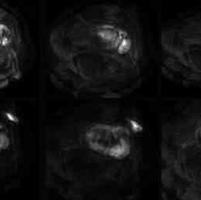

一例少见的神经鞘瘤

查看图片需登陆

一例少见的神经鞘瘤...

由 medjpg 发表于 2026-03-24 22:32